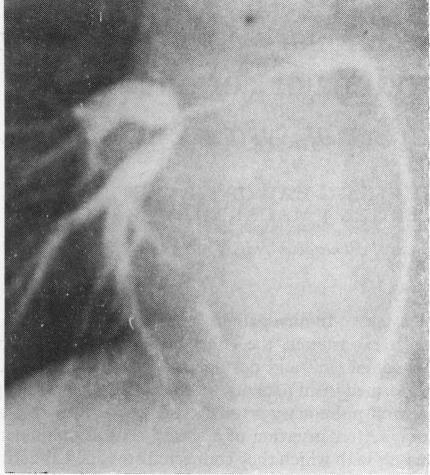

In nine patients with pulmonary atresia, ventricular septal defect, and major aortopulmonary collateral arteries, the effect of a systemic-pulmonary anastomosis on the lung was studied by comparison of pre- and postoperative cine angiograms. Selective injections into the collateral arteries were performed in all patients and the source of blood supply to each bronchopulmonary segment was sought. Central pulmonary arteries were present in six children and absent in three, as confirmed at thoracotomy. After insertion of a shunt, central pulmonary arteries increased in size, but the intrapulmonary vessels with which they connected remained abnormally small and were frequently stenosed. In addition, in each case the central pulmonary arteries increased flow to only five to 11 segments of lung. In the absence of central pulmonary arteries, shunting to a hilar or a lobar pulmonary artery increased perfusion to five to nine segments of lung per case. In all these three cases the pulmonary arteries at lobar level showed aneurysmal dilatation proximal to a severe stenosis. Sixty-eight per cent of collateral arteries were stenosed. The findings suggest that in this anomaly, when the central pulmonary arteries are hypoplastic, the intrapulmonary branches are also hypoplastic, emphasising the need for early surgical intervention to increase blood flow while the lung still has growth potential. Further, one collateral artery may connect with at least as many bronchopulmonary segments as does a central pulmonary artery, and the peripheral intrapulmonary arteries with which it connects may appear at least as normal angiographically as do vessels connected to central pulmonary arteries. These observations suggest that segments of lung connected to collaterals alone should, and sometimes can, be connected to central pulmonary arteries, the aim being to produce a unifocal blood supply as a prelude to total correction.

在9例患有肺动脉闭锁、室间隔缺损和主要体肺侧支动脉的患者中,通过比较术前和术后的电影血管造影来研究体肺分流术对肺的影响。对所有患者的侧支动脉进行了选择性注射,并寻找每个支气管肺段的血供来源。开胸手术证实,6名儿童存在中央肺动脉,3名儿童不存在中央肺动脉。插入分流管后,中央肺动脉尺寸增大,但其相连的肺内血管仍异常细小且常出现狭窄。此外,在每种情况下,中央肺动脉仅使5至11个肺段的血流增加。在没有中央肺动脉的情况下,向肺门或叶肺动脉分流使每例患者5至9个肺段的灌注增加。在所有这3例病例中,叶水平的肺动脉在严重狭窄近端呈瘤样扩张。68%的侧支动脉存在狭窄。这些发现表明,在这种畸形中,当中央肺动脉发育不全时,肺内分支也发育不全,这强调了在肺仍有生长潜力时尽早进行手术干预以增加血流量的必要性。此外,一条侧支动脉可能与至少和中央肺动脉一样多的支气管肺段相连,并且其相连的外周肺内动脉在血管造影上可能至少和与中央肺动脉相连的血管一样正常。这些观察结果表明,仅与侧支相连的肺段应该并且有时能够与中央肺动脉相连,目的是形成单一血供作为完全矫正的前奏。